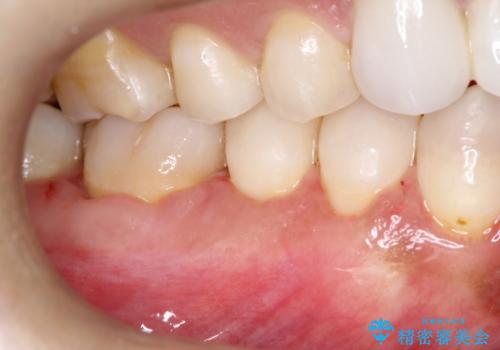

幸いなことに術後の痛みがほとんどなく、翌日には痛み止めも飲まずに済んだとのことでした。

治癒経過も良好で、患者様も満足されていました。また、知覚過敏も減ったとの事でした。